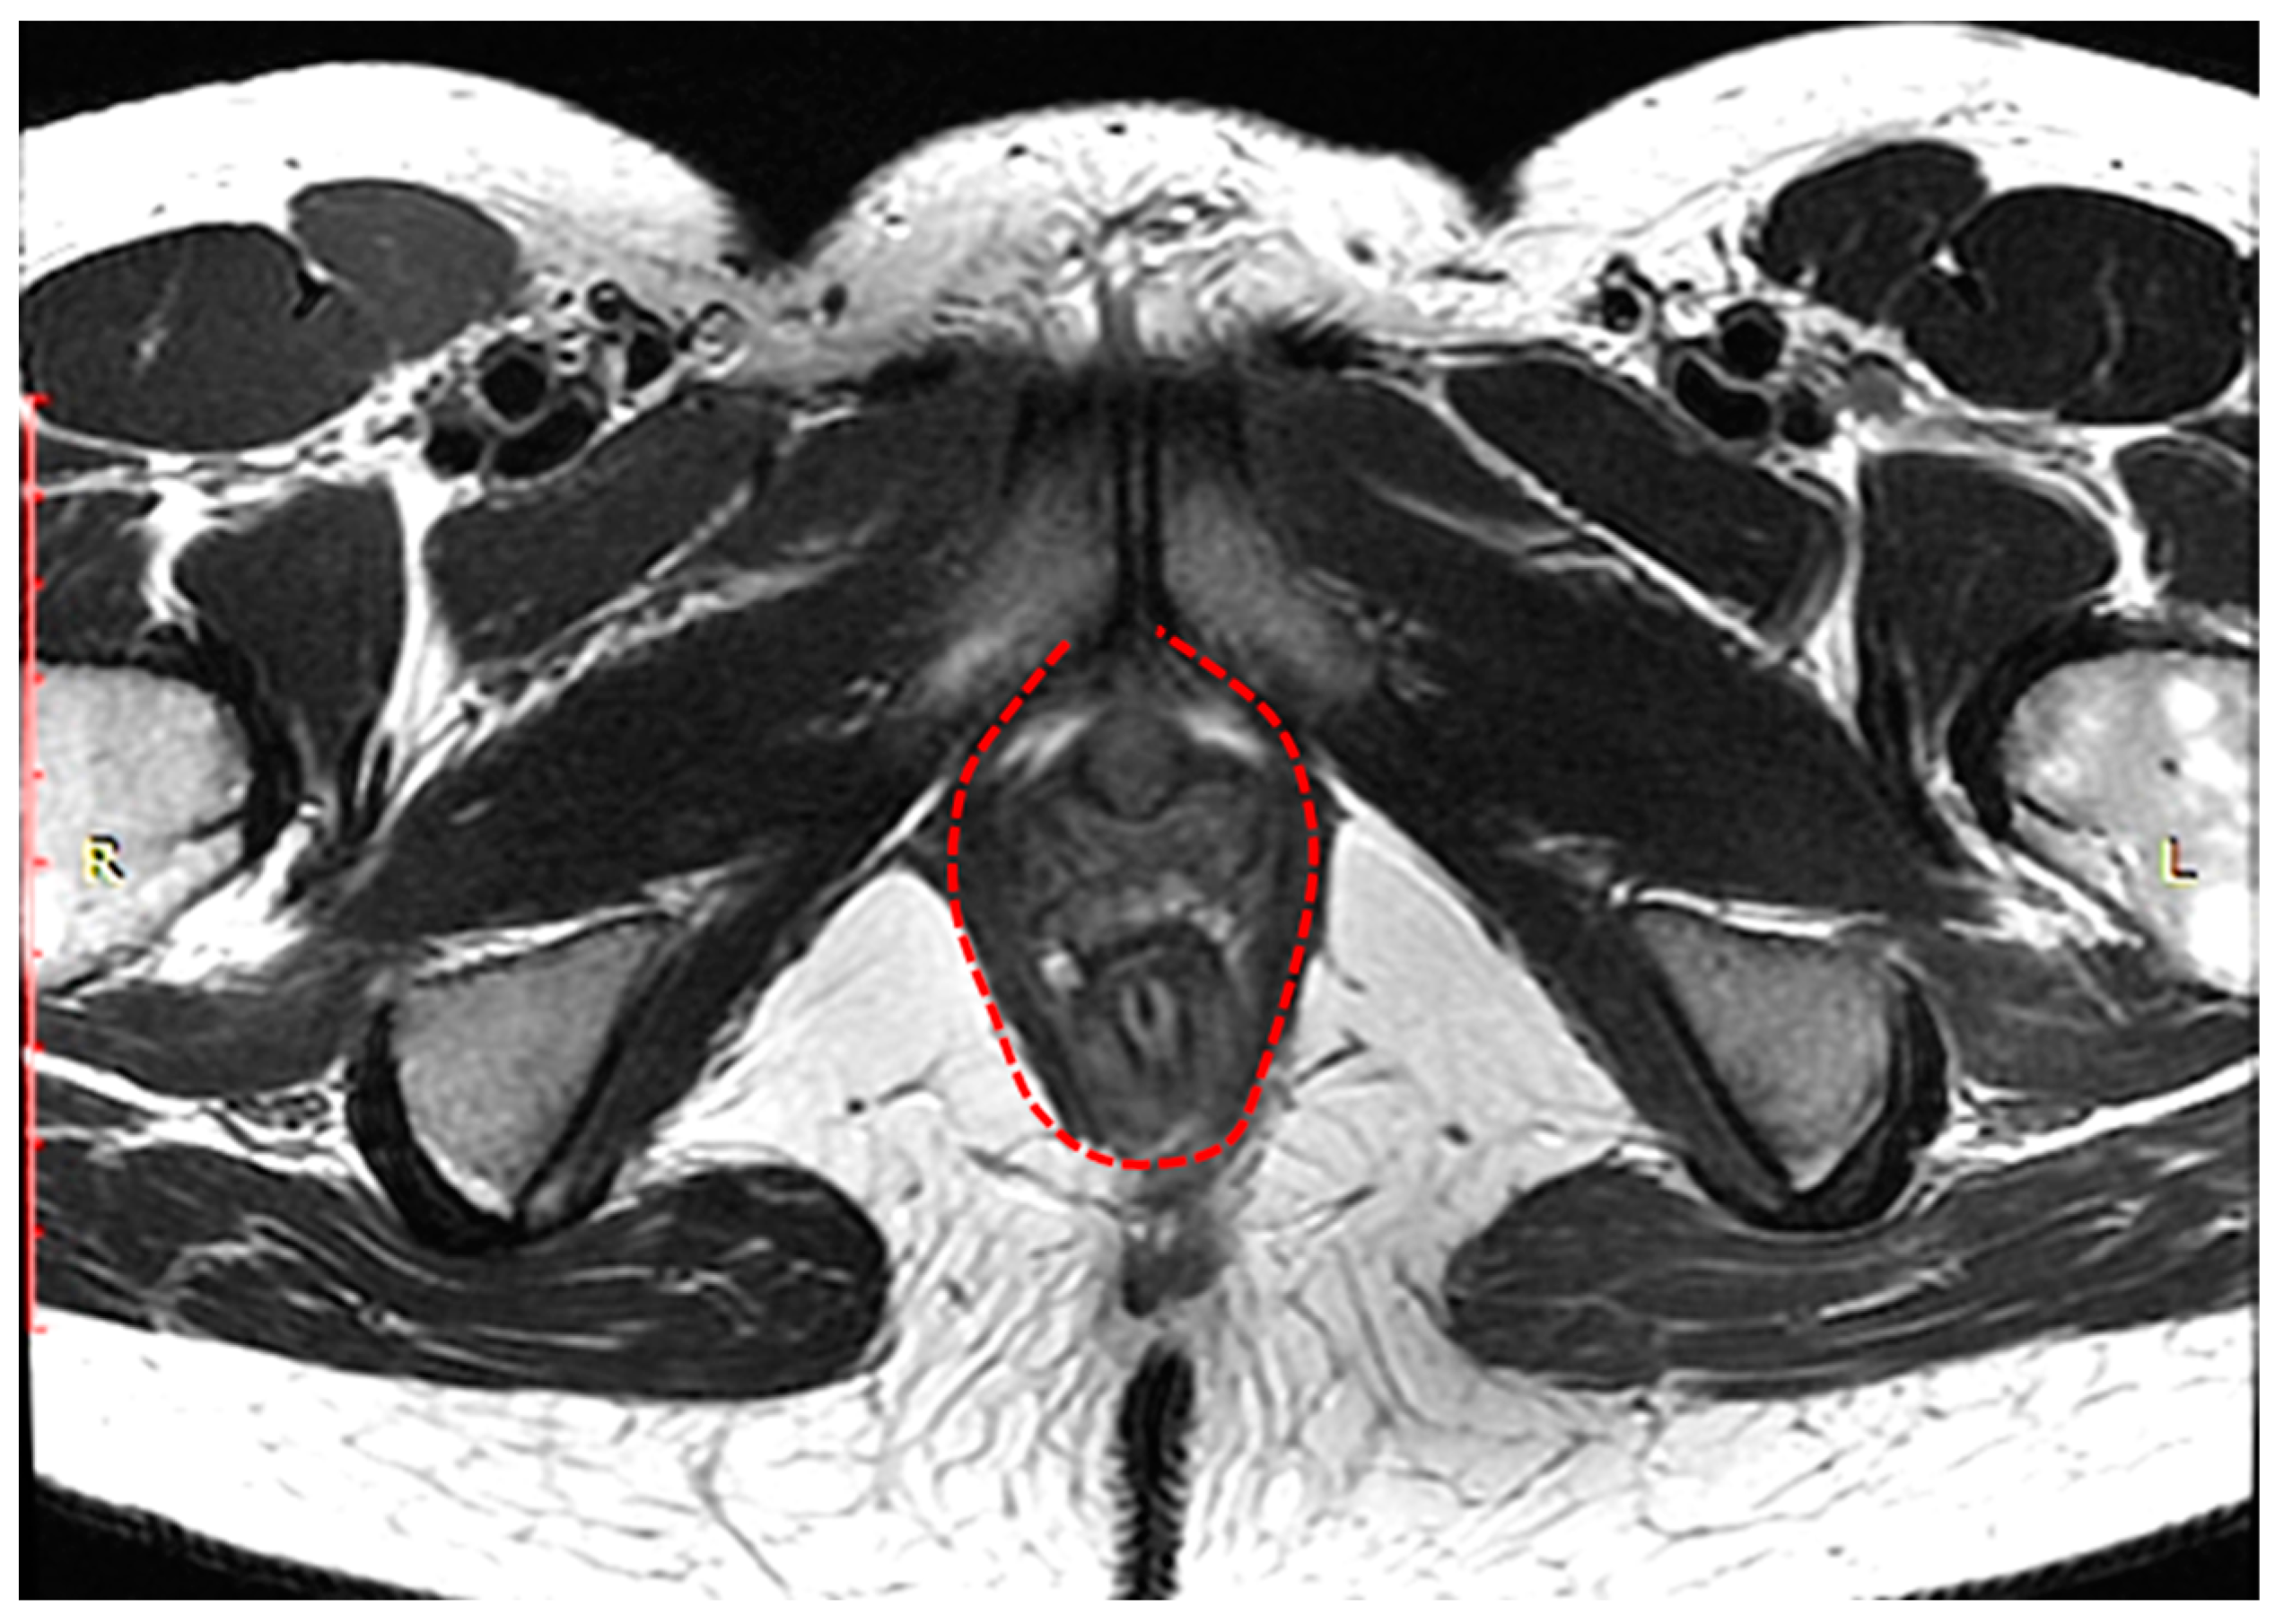

The complex that raises the anus consists of the pubo-rectal, pubo-coccygeal, and iliopsoas-coccygeal muscles. Of these, the pubo-rectal rectus muscle (Figure 1), which branches from the pubic bone in front and covers the anorectal transition forming the urogenital cleft, holds the pelvic floor organs together and adjoins the pubic bones, preventing prolapse of these organs, and also forms the angle between the anal canal and rectum and plays a role in retaining feces [35].

Figure 1. Pubo-rectal muscle U-shaped is highlighted in red, in the form of a loop covers urethra, vagina, and rectum, forming urogenital cleft.